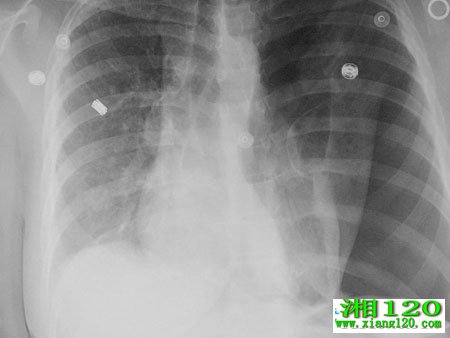

很多对气胸不了解,气胸就是肺无明显病变由胸膜下气肿泡破裂形成者称特发性气胸;继发于慢阻肺肺结核等胸膜及肺疾病者称继发性气胸。气胸会引发一系列身体不适,下面我们看下气胸反复发作怎么办?

1.青年人,多见于中学生,运动后发生,CT检查往往有肺大泡,如果反复发作2~3次以上,可以考虑手术切除肺大泡。

2.老年人,往往有慢性肺病史,如慢性阻塞性肺病或支气管哮喘等,多在疾病的发作期,因气道阻塞加重引起气胸,部分人可能有肺大泡。如反复发作引流效果不好时,也可考虑手术治疗。

气胸反复发作后,局部胸膜可以形成粘连,增厚,患者可以有胸部不适,疼痛或紧缩感,多出现在病变同一侧。随着时间的延长和呼吸运动的锻炼,多数症状会逐渐减轻或消失。你为右侧胸痛,不剧烈,如果疼痛与呼吸运动有关,也可能与既往的气胸有关。可以对症处理,如止痛、营养神经等,如果疼痛频繁或疼痛性质发生变化,可能与气胸无关,可能需要进一步检查。